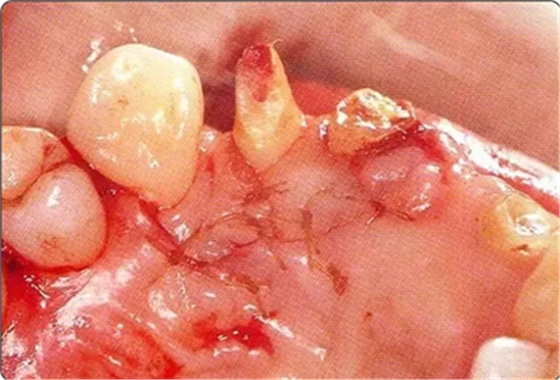

圖10-6 進行自體骨移植后的狀態(tài)

圖10-7 緊密貼合根面讓牙齦復(fù)位的狀態(tài)